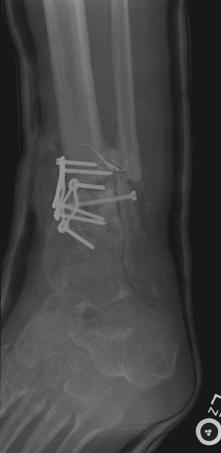

Post-corrective surgery X-Rays of the damaged right & left legs / ankles

The first two x-rays show Liam’s left ankle and pelvis prior to the accident. For comparison purposes it is interesting to see the

differences. The next x-rays were taken after the corrective surgery performed by Dr. Armendariz. Noticed that Dr. Armendariz has used tibia

bracing and also aligned the bone fragments of the left leg so that they could heal in the proper orientation. The external fixation has been

removed and Liam’s left foot has been returned to a more natural alignment.